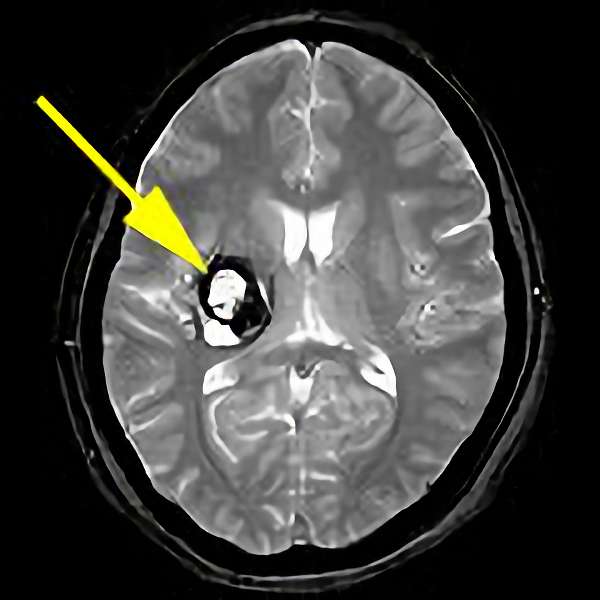

'19年11月

40代

富永

南田

基底核

海綿状血管腫

出血性

兵庫県の病院

より紹介

No.No.32 手術前1

No.No.32 手術前2

No.No.32 手術後1

No.No.32 手術後2

CT/MRにより完全に摘出されたことが確認された